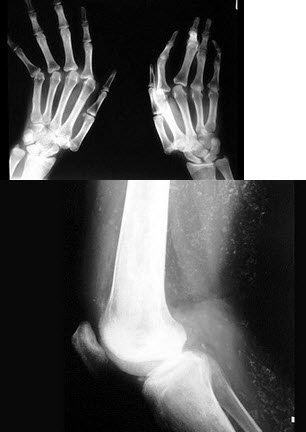

3、单项选择题 有关牛皮癣性关节炎的叙述中,哪项不正确()

32、单项选择题 关于原发性支气管肺癌,下列描述错误的是()

女,38岁,慢性疾病导致双手变形,颜面部可见蝶形红斑,结合图像,最可能的诊断是()

A.痛风

B.类风湿关节炎

C.骨麻风病

D.系统性红斑狼疮骨改变

E.骨梅毒